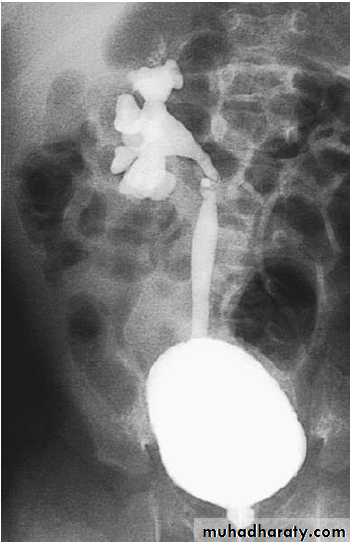

VSUG: showing

G 4 right VUR